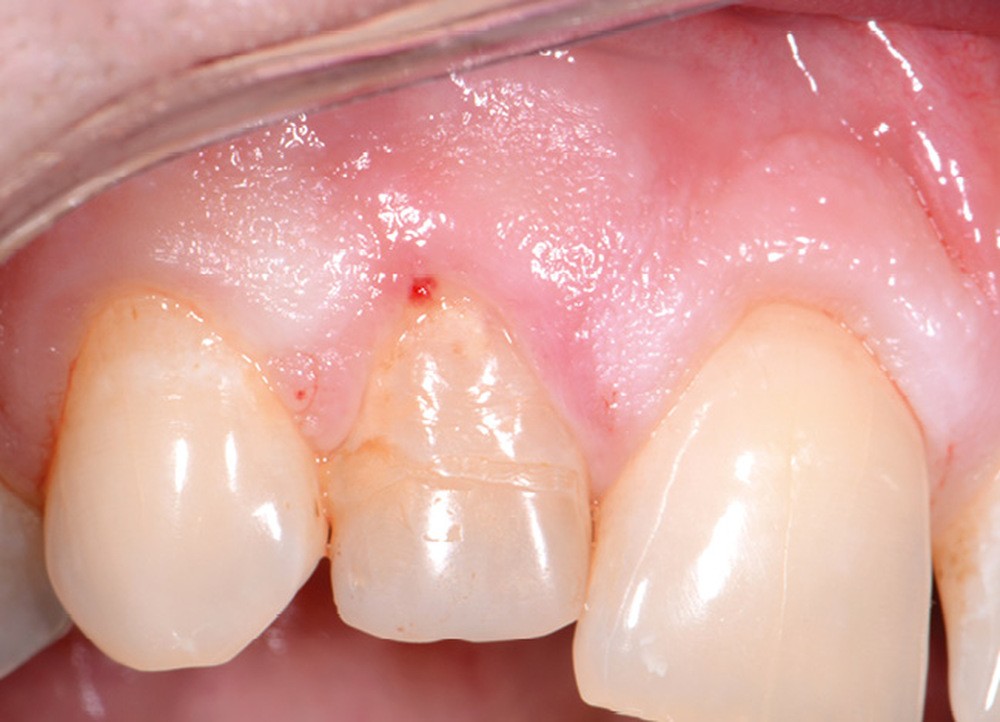

Perforation infra-osseuse avec accès visuel direct (fig. 3)

Ce type de perforation est également la plupart du temps iatrogénique et survient lors de la recherche ou de la mise en forme canalaire, lors de la préparation pour un logement de tenon radiculaire. Situées au niveau du plancher pulpaire des dents pluriradiculées, ou au niveau des entrées canalaires des dents monoradiculées ou pluriradiculées, il s’agit le plus souvent de perforations à quatre parois. Si la perforation survient en cours de traitement, elle doit être gérée immédiatement pour un meilleur pronostic (fig. 4). Néanmoins, il est important de prendre en compte l’épaisseur résiduelle du plancher. Si le plancher est trop fin, il ne sera pas possible d’envisager de traiter la perforation.